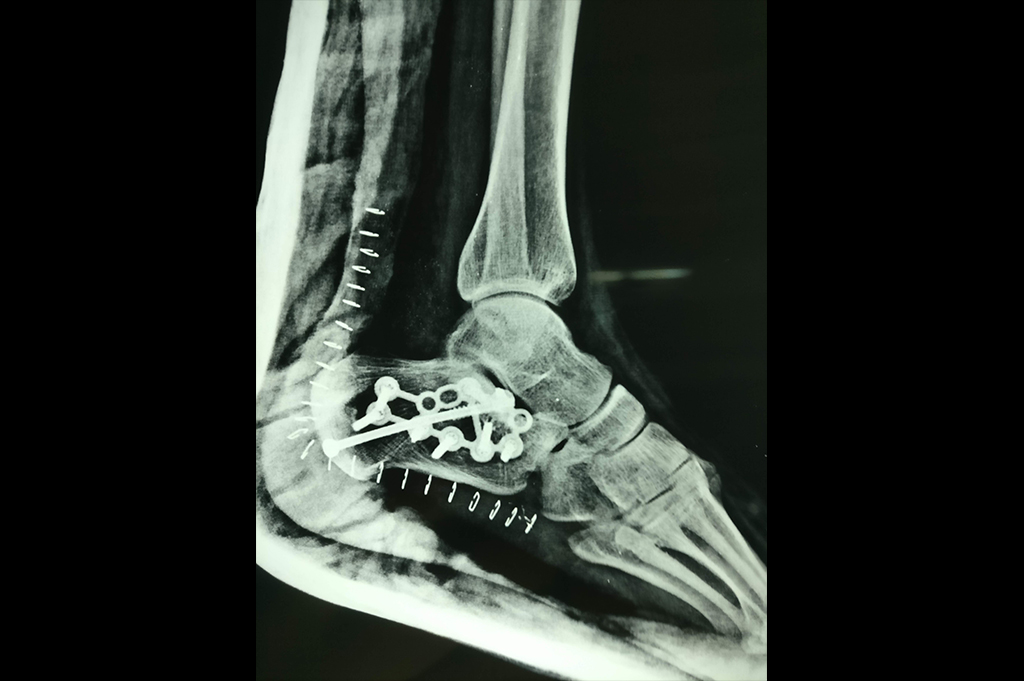

Ankle